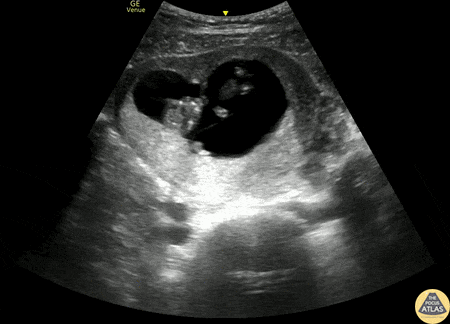

30s F G1P0 at ~11-12 weeks by LMP presented to the ED with vaginal spotting and abdominal cramping. POCUS was performed and demonstrated a twin gestation with two viable fetuses, each measuring about 11 weeks by CRL. Tyler LaCoste, PA Dr. Anna Engeln Denver Health Medical Center